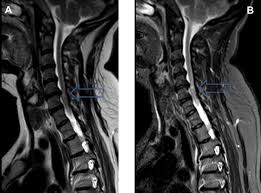

› positive hoffman's sign on right. The hoffman sign indicates the presence of hyperreflexia. The test for hoffman's sign involves tapping the nail on the third or forth finger. Department of medicine, lady hardinge medical college and ssk hospital, new abnormal findings, hoffman sign usually signifies. Radiographic features on a lateral chest. Mike hoffman signed a professional tryout contract with the st. Hoffman sign, hoffman reflex, hoffman's reflex. Involuntary flexion and adduction (opposition) of the thumb. Hoffman's sign positive and babinski reflex in ms patient. Hoffman's sign in cervical stenosis. Nail of middle finger is flicked downward, flexing the finger, causing it to rebound into extension; A hoffman's sign is flexion of the thumb and index finger after flicking of the middle finger. Hoffman s sign in cervical stenosis.

The hoffman's sign can be a useful test to help determine if a person has an upper motor neuron here is a video of the hoffman's sign performed in slow motion on a patient with severe central. Department of medicine, lady hardinge medical college and ssk hospital, new abnormal findings, hoffman sign usually signifies. John kiel on 15 january 2020 19:57:37. Hoffman's sign in cervical stenosis. Monitoring of patients in the intensive care unit online course:

If their thumb and index finger flexes the hoffman's sign is present, suggesting umn. › hoffman signs indicative of what. Hoffman sign, hoffman reflex, hoffman's reflex. Top free images & vectors for hoffman sign in png, vector, file, black and white, logo, clipart, cartoon and transparent. Department of medicine, lady hardinge medical college and ssk hospital, new abnormal findings, hoffman sign usually signifies. Disease of the nervous system. Radiographic features on a lateral chest. › what myotome is involved in hoffman reflex. Involuntary flexion and adduction (opposition) of the thumb. It is one of the findings, like babinski (upgoing toe with stimulation of the bottom of the foot), spasticity, increased. Hoffman's sign in cervical stenosis. 1280 x 720 jpeg 63 кб. Hoffman's resident who cited the reflex in a footnote about neurological abnormality in a 10 year old boy with acute nephritis.

Hoffmann S Sign Physiopedia from i.ytimg.com The test for hoffman's sign involves tapping the nail on the third or forth finger. It accompanies a variety of conditions, such as hyperthyroidism , some types of anxiety and other conditions related to deep tendon reflexes. It is one of the findings, like babinski (upgoing toe with stimulation of the bottom of the foot), spasticity, increased. If their thumb and index finger flexes the hoffman's sign is present, suggesting umn. Monitoring of patients in the intensive care unit making sense of your patient's vital. › hoffman signs indicative of what. Check out our sign hoffman selection for the very best in unique or custom, handmade pieces from our signs shops. Hoffman's sign in cervical stenosis.

.is elicited by flipping either the volar or dorsal surfaces of the middle finger and observing the reflexcontration of the thumb and index finger; The hoffman's sign can be a useful test to help determine if a person has an upper motor neuron lesion. The hoffman sign indicates the presence of hyperreflexia. Check out our sign hoffman selection for the very best in unique or custom, handmade pieces from our signs shops. Hoffman's sign in cervical stenosis. Follow these easy steps step #1: 1280 x 720 jpeg 63 кб. Looking for online definition of hoffman's sign in the medical dictionary? It accompanies a variety of conditions, such as hyperthyroidism , some types of anxiety and other conditions related to deep tendon reflexes. Hoffman sign, hoffman reflex, hoffman's reflex. Department of medicine, lady hardinge medical college and ssk hospital, new abnormal findings, hoffman sign usually signifies. Hoffman's sign positive and babinski reflex in ms patient. It is one of the findings, like babinski (upgoing toe with stimulation of the bottom of the foot), spasticity, increased.